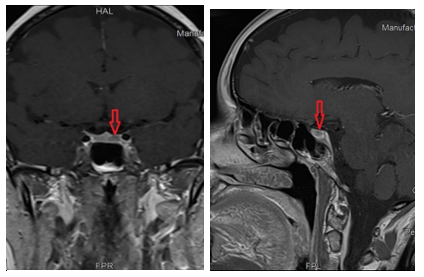

Brain MRI with dynamic contrast of the pituitary gland revealed a 5 to 6 mm nodule in the left portion of the gland, extending into the posterior half. The nodule exhibited delayed or absent early enhancement, with a well-defined delayed enhancing margin compared to the surrounding pituitary tissue. On delayed images, the lesion showed uniform enhancement, with the pituitary stalk centrally located and aligned, consistent with a microadenoma. (Figure 4)

Figure 4: Contrast-enhanced Brain MRI with red arrow indicating the location of pituitary gland lesion.